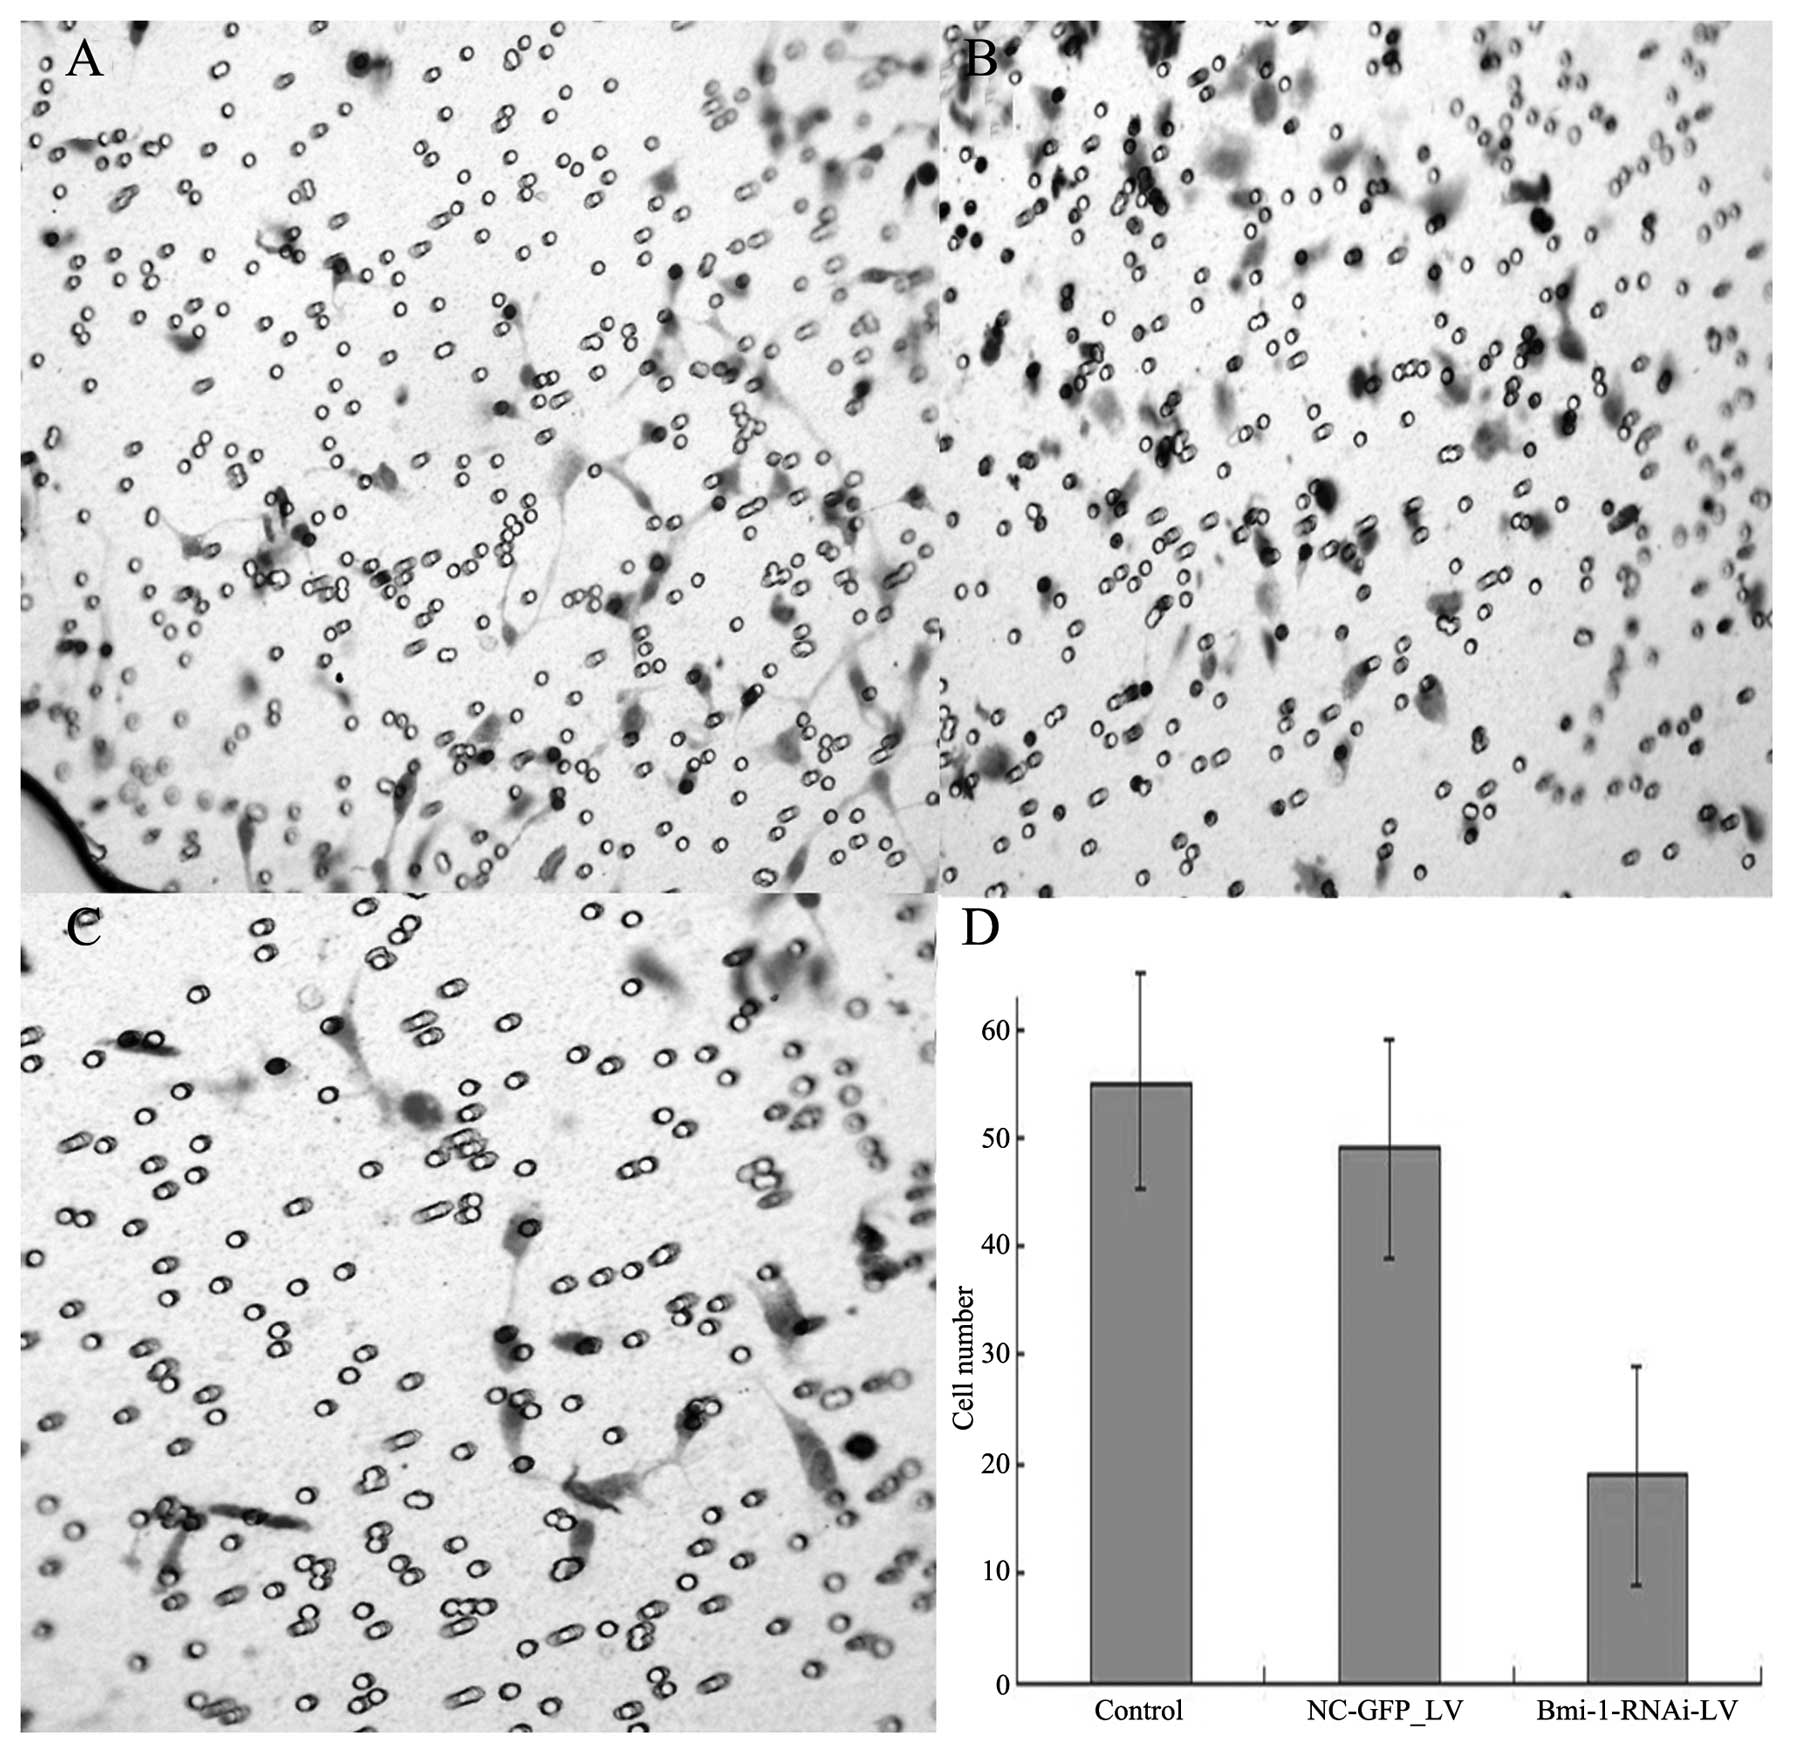

After the cultivation of the cells for 48 h, invasions of 18.5±3.8, 55.6±11.3, and 49±13.5 cells/field of view through the porous Transwell membranes were observed for the Bmi-1-RNAi-LV, control and NC-GFP-LV group, respectively (t=12.62, P<0.01) (Fig. 7).

Figure 7

Effect of Bmi-1 silencing on the migration of HEp-2 cells. (A) HEp-2 cells transfected with mock (control). (B) Scrambled nucleotide control siRNA (NC-GFP-LV). (C) HEp-2 cells transfected with Bmi-1 siRNA (Bmi-1-RNAi-LV). (D) Statistical analyses revealed that Bmi-1 knockdown by Bmi-1-RNAi-LV transfection (Bmi-1 KD groups) significantly inhibited cell motility.